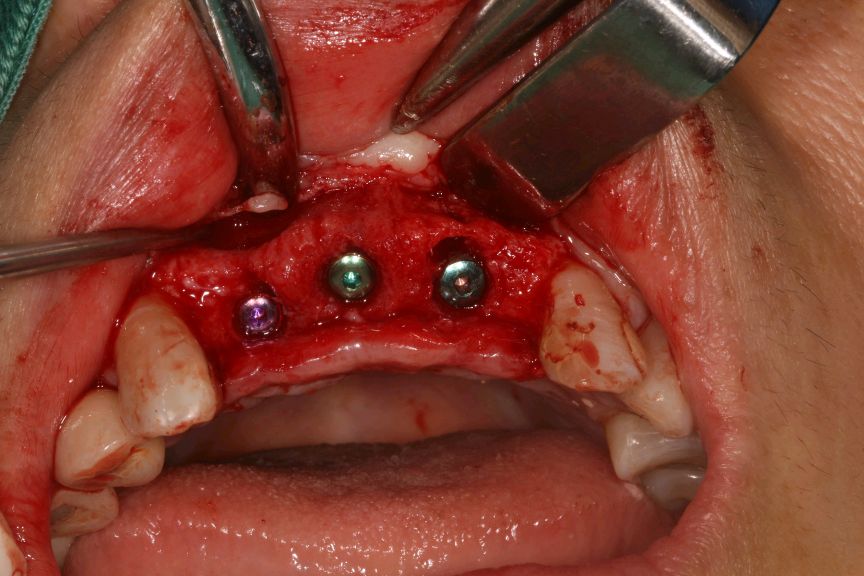

向患者交代病情、治疗计划、费用、预后等,患者知情并同意治疗。,抽静脉血20ml,12植入欧美 hiossen 种植体3.5*11.5mm,11.21植入欧美 hiossen 种植体4.0*11.5mm上覆盖螺丝,颊侧骨缺损区植入人工骨粉 傲骨0.5g及 CGF ,并盖百傲膜及 CGF 膜,严密缝和。二期三期如期进行与近日佩戴牙齿。

术中